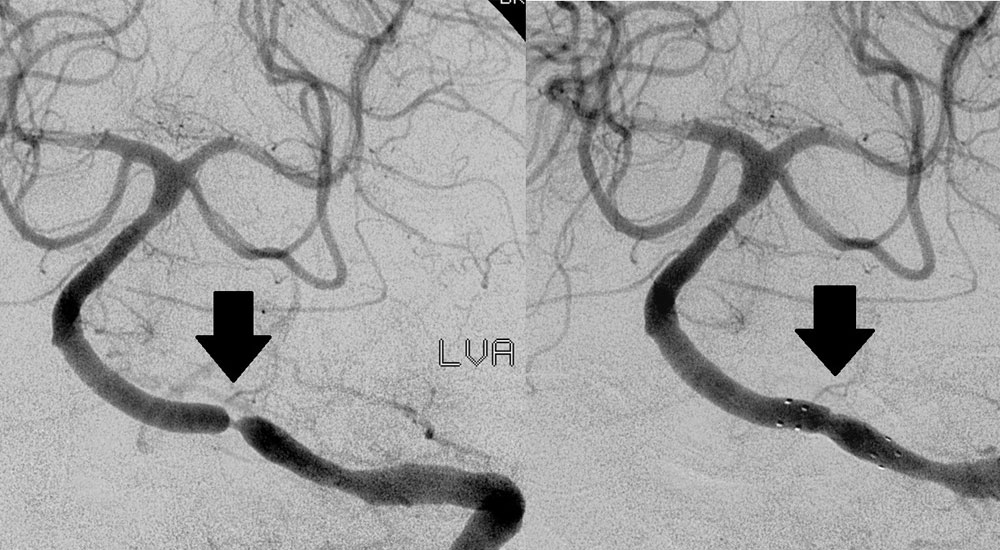

When used to treat atherosclerosis in either the carotid arteries or intracranial arteries, stents act as a permanent implant that opens these blocked arteries, allowing improved blood to flow to the brain. Angioplasty (a procedure to widen blockages) along with placement of a stent may be an appropriate stroke treatment or stroke prevention option for some people who have had a stroke or transient ischemic attack (TIA). In angioplasty, a balloon catheter (hollow tube) opens the blocked artery to improve blood flow. The stent provides a barrier to reduce the risk of recurrent narrowing of the artery and also supports the artery wall. Sometimes the doctor may use angioplasty to widen the affected area first; in other cases, angioplasty is not used before stent placement.